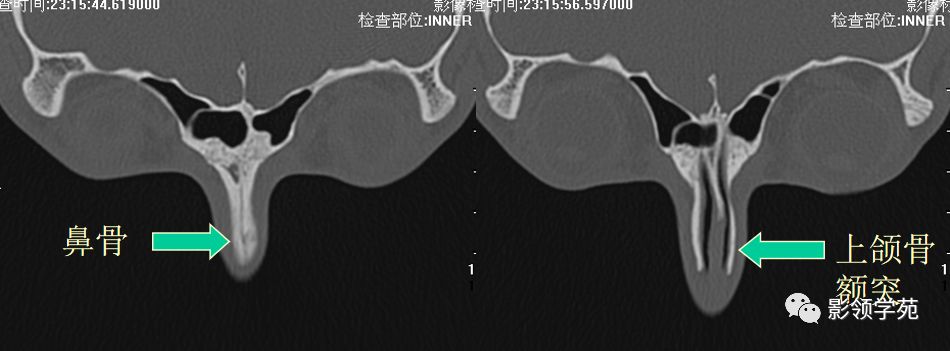

鼻骨横断面HRCT

鼻骨冠状面HRCT